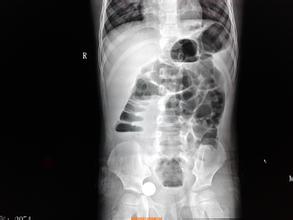

為何要特別注意老年人腸梗阻

腸梗阻是一種很多原因都可以引起的疾病,有很多表現(xiàn),根據(jù)它的表現(xiàn)的不同,腸梗阻可以分為不同的類(lèi)型。

從腸梗阻的病因中我們可以看出,腫瘤是引起腸梗阻的原因之一。而且近二十年來(lái),隨著我國(guó)人民生活水平的提高、飲食習(xí)慣的改變,胃腸道腫瘤的發(fā)生率有明顯升高,在引起腸梗阻的病因中,腫瘤所占的比例也越來(lái)越高。老年人是腫瘤的高發(fā)人群,因此,如果老年人發(fā)生不明原因的腸梗阻,應(yīng)特別引起注意。有些老年人在生活中漸漸的出現(xiàn)食欲不佳,腹部脹氣,有時(shí)出現(xiàn)腹部包塊,排氣排便障礙,但并不引起注意,自以為是人老了,器官功能減退,未能引起足夠的重視。有時(shí)還因?yàn)榧毙阅c梗阻住院治療,經(jīng)過(guò)輸液抗炎治療后,病情緩解,也不進(jìn)行進(jìn)一步的檢查,就回家休養(yǎng)。這樣,在半年或一年以后,往往出現(xiàn)再次腸梗阻而進(jìn)一步診治時(shí)才發(fā)現(xiàn)患了消化道腫瘤,耽誤了病情;有的則可能是因?yàn)槟c梗阻,進(jìn)行急診手術(shù)時(shí)才發(fā)現(xiàn)由腫瘤引起。當(dāng)出現(xiàn)這些情況時(shí),說(shuō)明病情已發(fā)展至晚期,患者手術(shù)后的生存時(shí)間及質(zhì)量將受到嚴(yán)重影響。

因此,當(dāng)老年人出現(xiàn)腸梗阻后,一定要引起重視,仔細(xì)檢查,回憶近一段時(shí)間的飲食及大便情況,必要時(shí)需要進(jìn)行胃鏡、纖維結(jié)腸鏡和鋇灌腸等輔助檢查,以排除腸道腫瘤的可能,同時(shí)采取及時(shí)有效的治療措施。